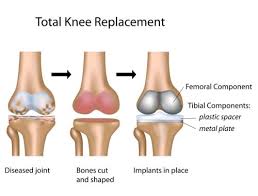

Knee replacement surgery in Narsinghpur Knee replacement surgery in Narsinghpur is an advanced orthopedic procedure designed to relieve severe knee pain and restore mobility in patients suffering from arthritis,...

Knee replacement surgery in Shahdol Introduction Knee replacement surgery in Shahdol is a reliable solution for individuals struggling with chronic knee pain, stiffness, and restricted movement. As joint conditions...

Knee replacement surgery in Umaria Knee replacement surgery in Umaria is an advanced orthopedic procedure designed to restore mobility and reduce chronic knee pain caused by arthritis, injury, or...

Knee replacement surgery in Panna Introduction Knee replacement surgery is an advanced orthopedic procedure designed to restore mobility and reduce chronic knee pain caused by severe joint damage. Moreover,...

Knee Replacement Surgery in Tikamgarh Knee replacement surgery in Tikamgarh is an advanced orthopedic procedure that helps patients regain mobility, reduce chronic knee pain, and improve overall quality of...

Knee Replacement Surgery in Shajapur Knee replacement surgery in Shajapur offers patients a chance to regain mobility and alleviate chronic knee pain caused by arthritis, injury, or degeneration. Individuals...